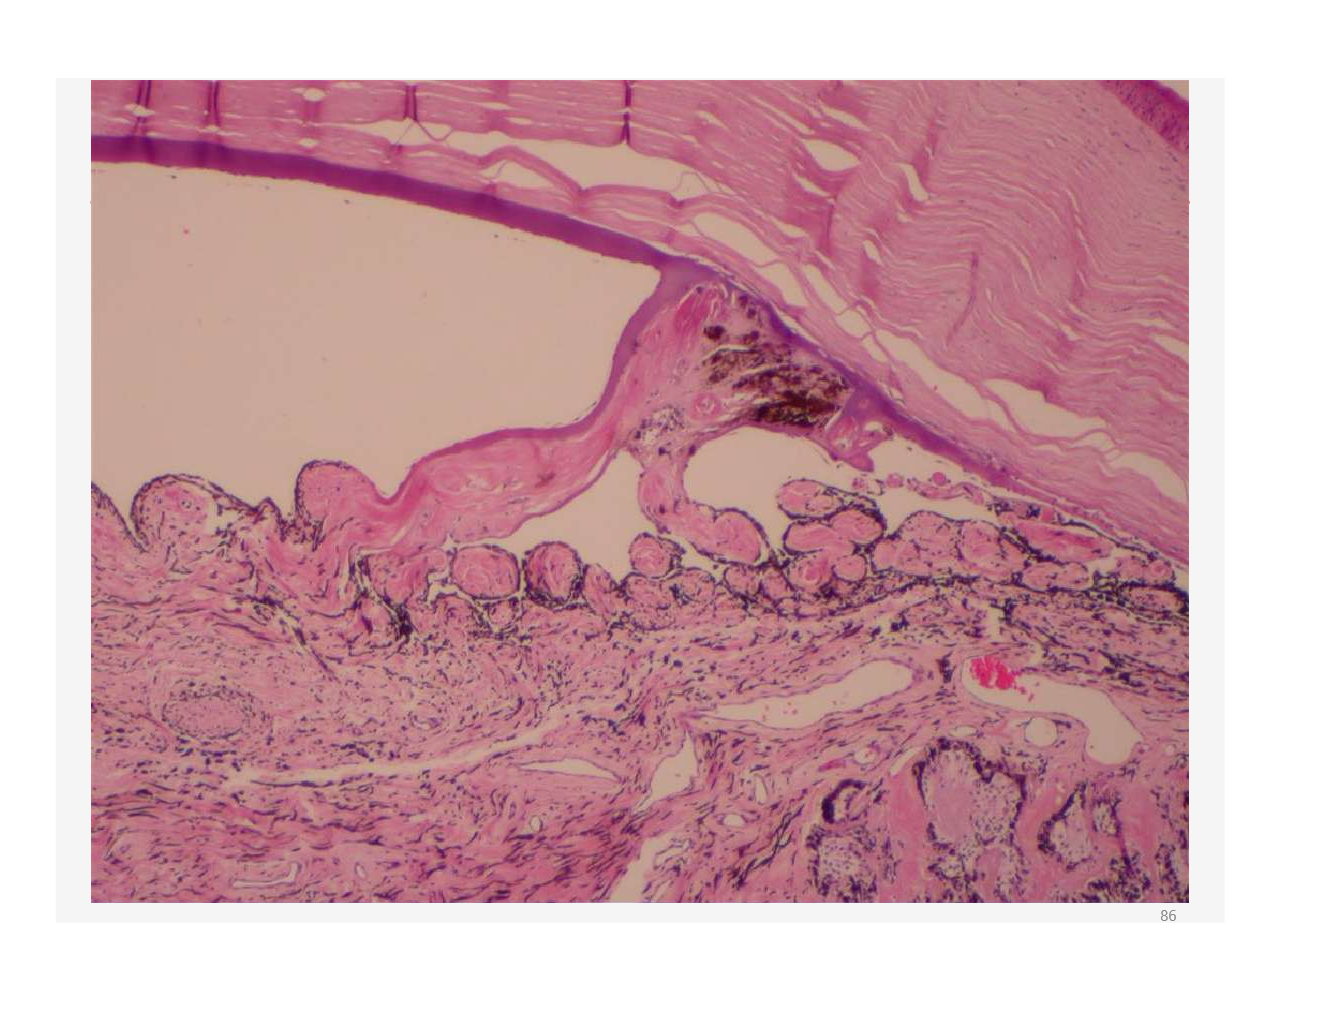

what is this?

developed from uveitis